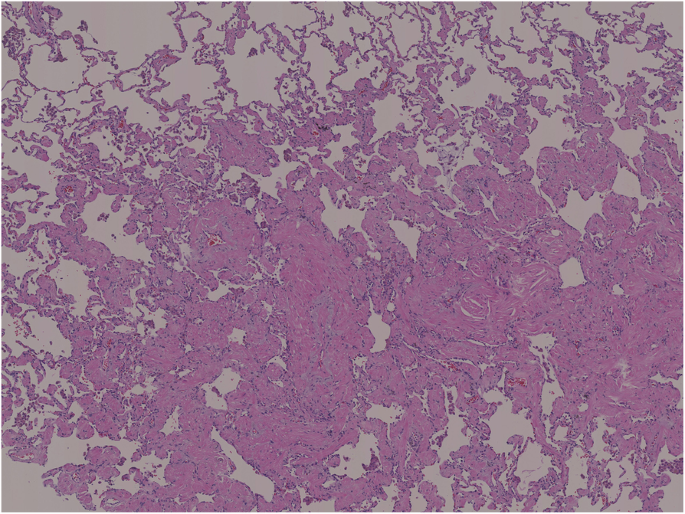

A 72-year-old woman with no symptoms had a medical checkup, and a subsequent CT revealed a nodular shadow in the left lower lobe (Fig. 3). 18FDG-PET was not performed preoperatively because the lesion was small. We suspected a primary lung cancer, and the patient consented to a thoracoscopic partial resection of the left lower lobe for diagnosis and treatment. Pathological findings revealed a 5-mm nodule with an unclear boundary. Hematoxylin and eosin staining revealed collagen fibers, bronchiolar metaplasia, lymphocyte-induced inflammatory cell infiltration, and smooth muscle dendritic growth with foamy histocytes (Fig. 4), Immunohistochemistry revealed desmin and alpha-smooth muscle actin positivity. A diagnosis of NSMP was made. The patient received no postoperative treatment, and no recurrence has been observed.

The histopathological features of NSMP resemble those of hamartoma and leiomyoma [2], as all three lesions exhibit a proliferation of spindle-shaped cells and smooth muscle upon hematoxylin and eosin staining. Although an immunohistochemical analysis of NSMP reveals desmin and SMA positivity, this is not useful for differentiation from hamartoma or leiomyoma. The difference is that NSMP lesions contain more smooth muscle compared to hamartomas. NSMP also differs from leiomyoma in lesion size. Although no specific definition or standard of NSMP has been established, pathological findings indicate that NSMP exhibits dendritic smooth muscle proliferation, which results in unclear edges. This margin type clearly differs from the smooth margins of leiomyomas and hamartomas. In our cases, the smooth muscle tissue within the lesions appeared dendritic, with an undefined border. In addition, no tissue growth other than smooth muscle tissue was observed in the lesions, which was unlike a hamartoma. These pathological findings led us to diagnose NSMP in both cases. We speculated that the GGO observed around the nodules on preoperative CT was due to the spread of the smooth muscle tissue in a dendritic manner.